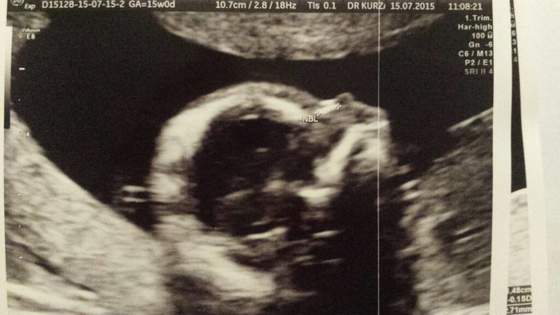

proszę :) śmiechem żartem wg wczorajszego usg miałam wczoraj 16t 0 dni :) a wg om 15t 0 dni :)

• 1437063519959.jpg

1437063519959.jpg

20,7 KB · Wyświetleń: 53